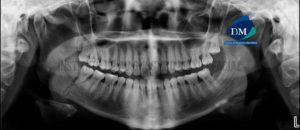

Paciente de sexo masculino de 54 años acude al Instituto de Diagnóstico Maxilofacial para evaluación del sector dentario posterior. A la evaluación de la radiografía